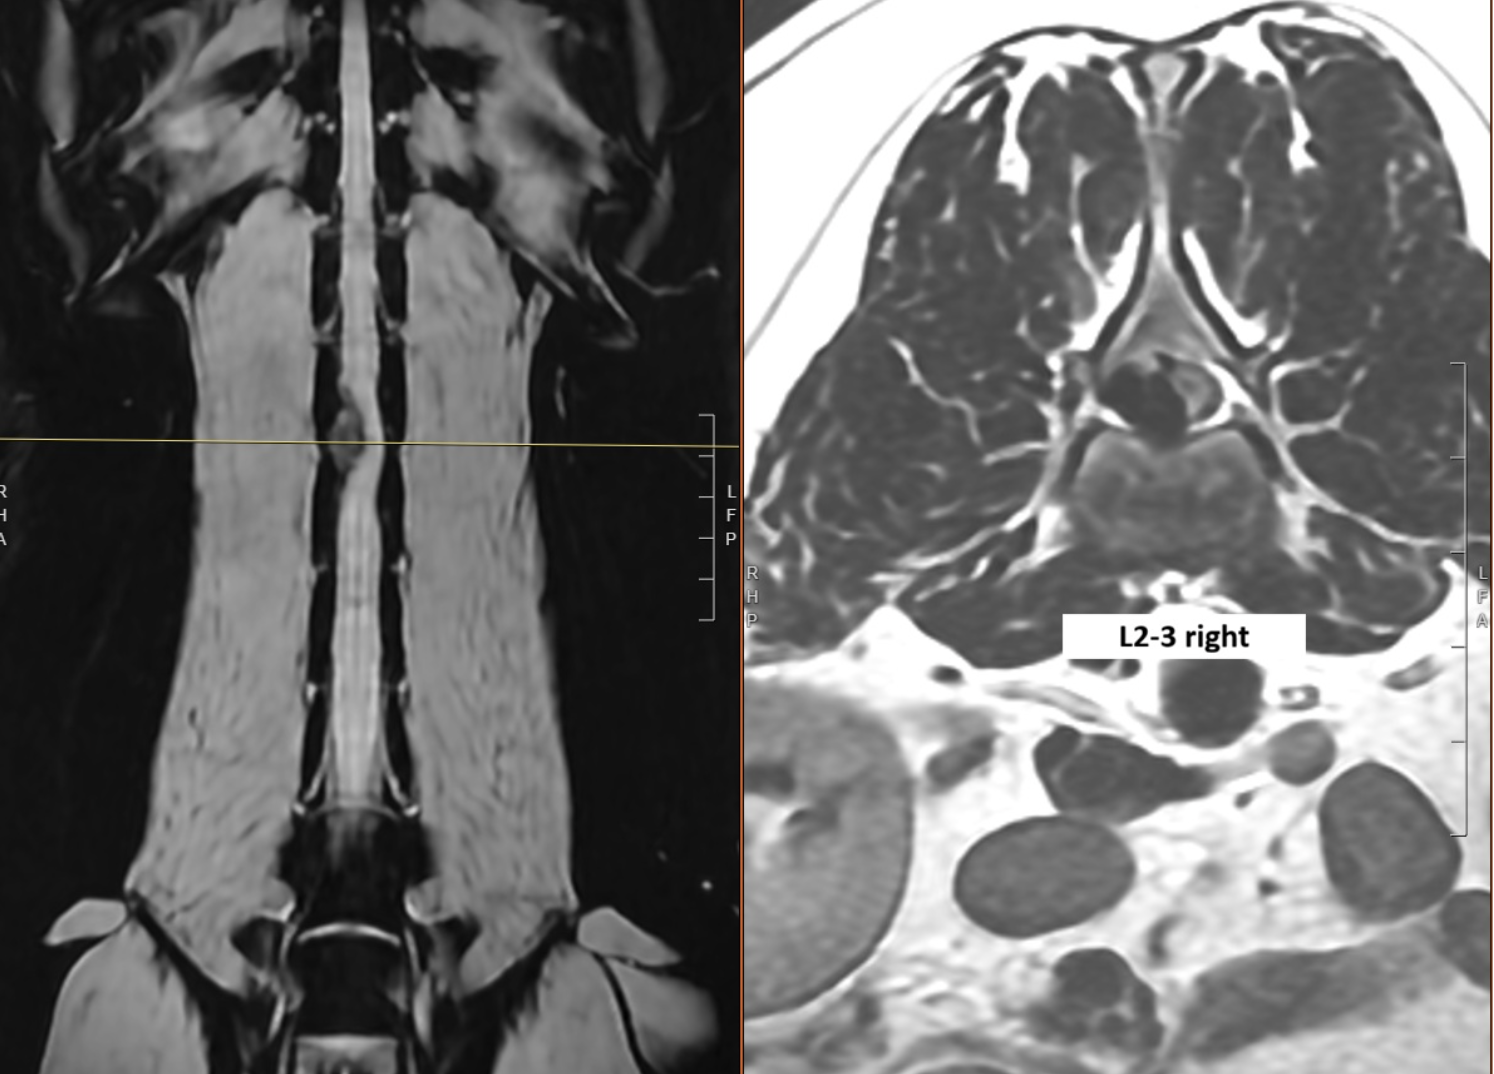

When Dr. Jay McDonnell assessed him, Bodhi was in significant pain, unable to move his hind legs, had normal reflexes, and could feel his toes. We considered this an emergency and proceeded to perform a spinal MRI, which revealed an intervertebral disc extrusion — a ruptured disk — between the second and third lumbar vertebrae (L2-L3), causing severe compression of the spinal cord.

Left Image: A coronal view of Bodhi’s back showing a large, right-sided, extradural compression at L2-3.

Right Image: An axial view at the level of the line. The spinal cord is severely compressed to the left (grey tissue) by the large right-sided disk (black tissue).